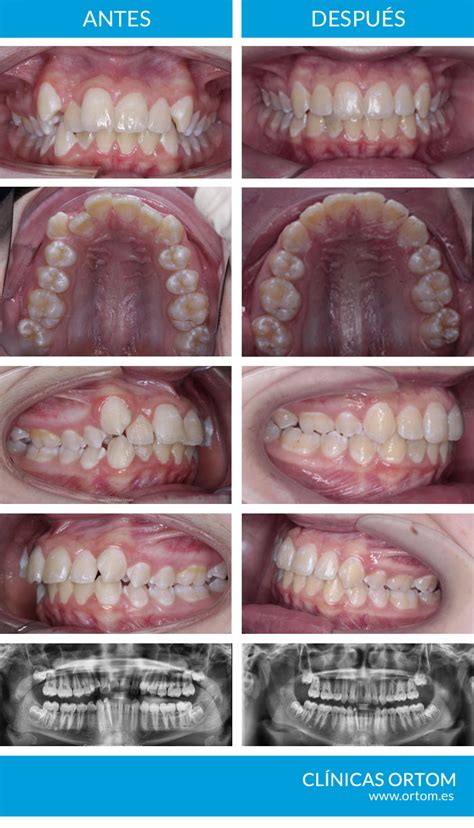

El tratamiento de ortodoncia es una práctica común y efectiva para corregir problemas de alineación dental y mejorar la salud bucal. Si bien es normal que se muevan los dientes con ortodoncia, la pérdida de dientes es extremadamente rara si el tratamiento es realizado y supervisado por un especialista. El miedo a que se te caiga algún diente por llevar ortodoncia es una preocupación bastante común entre quienes consideran iniciar un tratamiento para alinear sus dientes, ya sea con brackets o con alineadores invisibles como Invisalign. Hoy quiero responder a esta pregunta y explicarte por qué sucede, qué puedes esperar durante el proceso y cómo manejamos estas situaciones en nuestra clínica.

La respuesta breve es que, en condiciones normales y con una supervisión profesional adecuada, los dientes no se caen por usar ortodoncia. Tanto brackets como alineadores están diseñados para mover los dientes de manera controlada y segura. La ortodoncia emplea diferentes tipos de aparatos fijos y removibles, como los brackets metálicos, cerámicos y linguales, así como los alineadores transparentes.

La sensación de que los dientes se aflojan durante un tratamiento de ortodoncia es, en la mayoría de los casos, completamente normal. Aunque puede parecer preocupante, en realidad es una parte esencial del proceso de corrección dental. El principio básico de la ortodoncia, tanto si es con brackets como con Invisalign, es mover los dientes para alinearlos de forma correcta.

Para lograr esto, el aparato ortodóncico ejerce una fuerza controlada sobre los dientes, lo que genera un movimiento gradual. Este movimiento es completamente normal y necesario durante el tratamiento. Incluso es habitual notar una ligera movilidad dental durante este proceso. Los dientes flojos en ortodoncia son una señal de que las fuerzas aplicadas están surtiendo efecto, pero no implican que se vayan a caer.

Cuando los dientes se mueven, el hueso que los sostiene también debe cambiar. El proceso de remodelación ósea es lento, lo que significa que los dientes pueden sentirse flojos al principio, pero con el tiempo, el hueso se va solidificando y fijando los dientes en su nueva posición. Este proceso es completamente natural y forma parte de la razón por la cual la ortodoncia es tan efectiva.

Es importante entender que el movimiento de los dientes con ortodoncia no solo busca mejorar la estética de la sonrisa, sino también la funcionalidad de la mordida y la salud dental general. Los dientes se colocan en una posición óptima para facilitar la masticación, evitar problemas de encías o desgaste dental y corregir cualquier maloclusión que pueda haber.